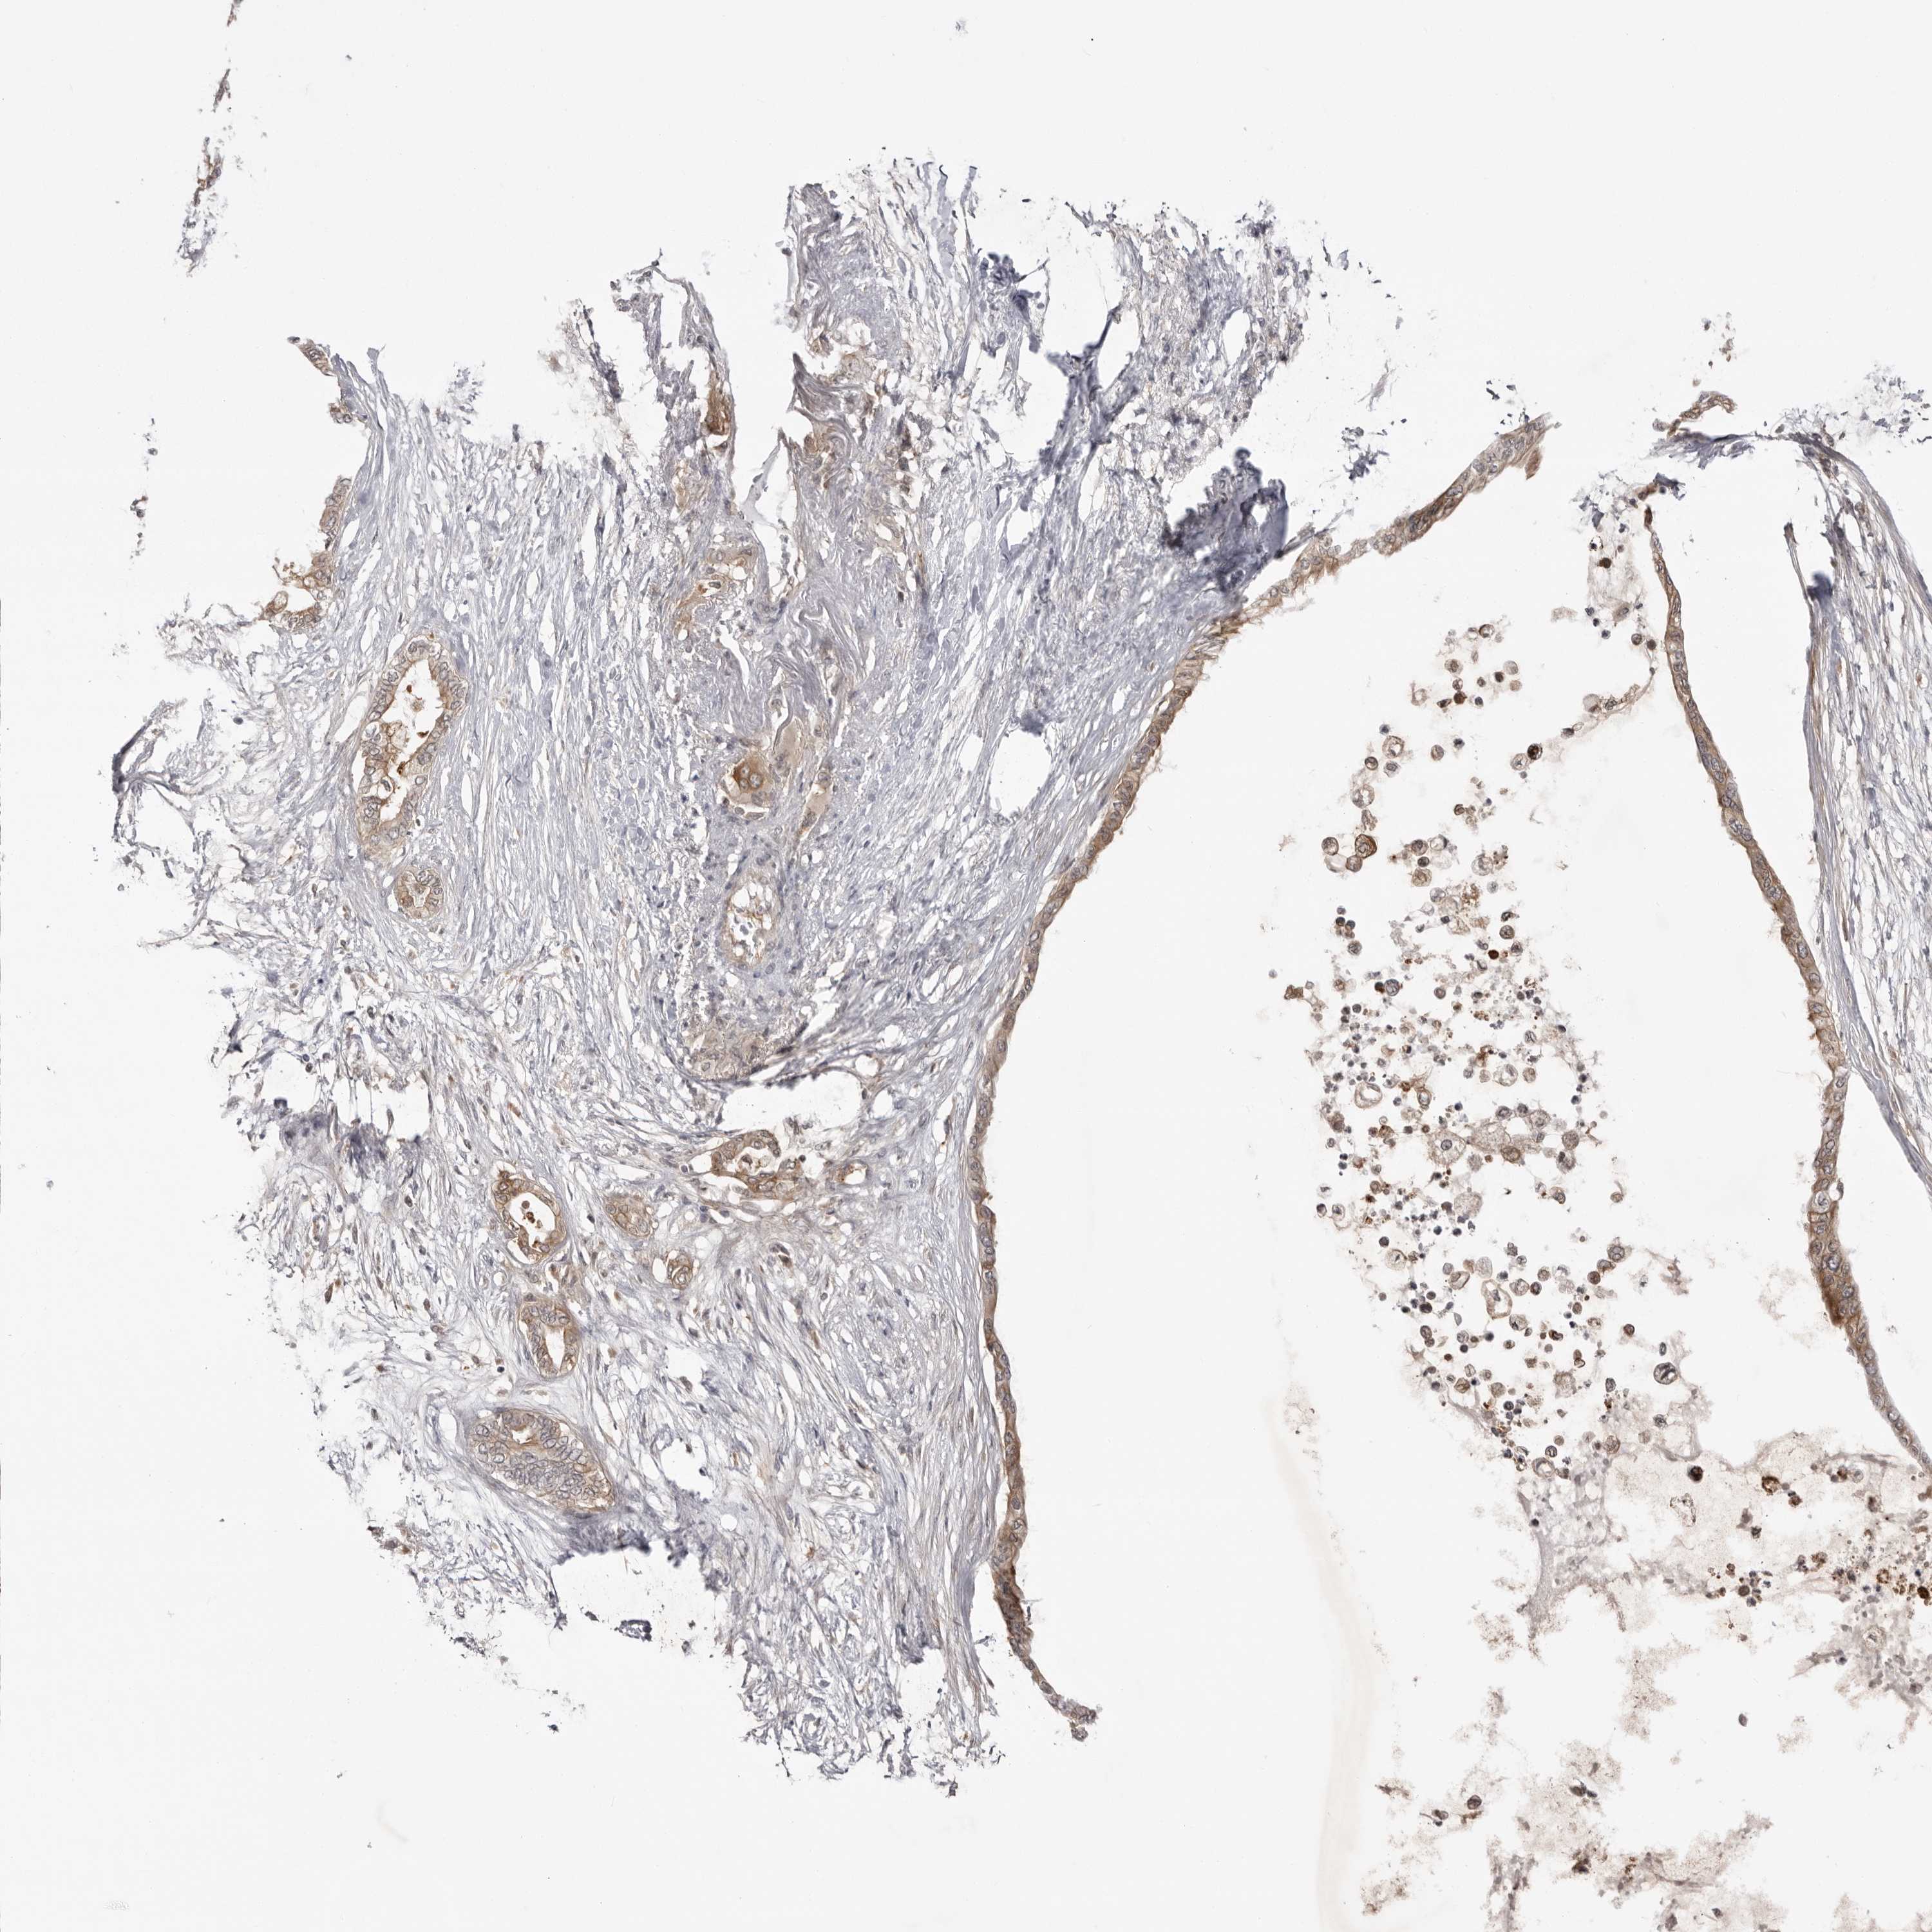

PANCREATIC CANCER - Protein expressioni

A mouse-over function shows sample information and annotation data. Click on an image to view it in a full screen mode. Samples can be filtered based on level of antibody staining by selecting one or several of the following categories: high, medium, low and not detected. The assay and annotation is described here.

Note that samples used for immunohistochemistry by the Human Protein Atlas do not correspond to samples in the TCGA dataset.

Antibody stainingi

Antibody staining in the annotated cell types in the current human tissue is reported as not detected, low, medium, or high, based on conventional immunohistochemistry profiling in selected tissues. This score is based on the combination of the staining intensity and fraction of stained cells.

Each image is clickable and will lead to virtual microscopy that enables deeper exploration of all samples and also displays staining intensity scores, fraction scores and subcellular localization as well as patient and tissue information for each sample.

Antibody HPA023389

Antibody HPA027762

Staining

High

Medium

Low

Not detected

Intensity

Strong

Moderate

Weak

Negative

Quantity

>75%

75%-25%

<25%

None

Location

Nuclear

Cytoplasmic/membranous

Cytoplasmic/membranous,nuclear

Adenocarcinoma, NOS